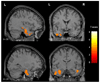

Main outcome measure: Patterns of gray matter loss in the MCI groups compared with control subjects, assessed using voxel-based morphometry.

Results: Subjects in the amnestic single- and multiple-domain groups showed loss in the medial and inferior temporal lobes compared with control subjects, and those in the multiple-domain group also had involvement of the posterior temporal lobe, parietal association cortex, and posterior cingulate. Subjects in the nonamnestic single-domain group with language impairment showed loss in the left anterior inferior temporal lobe. The group with attention/executive deficits showed loss in the basal forebrain and hypothalamus. No coherent patterns of loss were observed in the other subgroups.